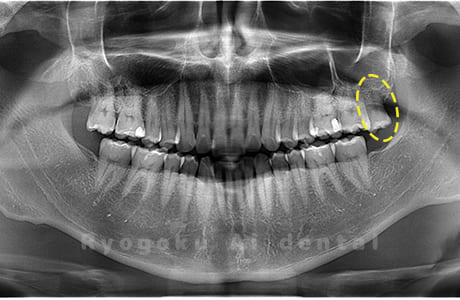

斜めに生えている親知らず

親知らずが斜めに生えて隣の歯にぶつかって圧迫してしまうタイプです。

このタイプが最も多いです。このタイプは虫歯になりやすいだけでなく、隣の歯を圧迫し、咬み合わせや歯並びに影響が出る場合もあるので抜歯をおすすめします。